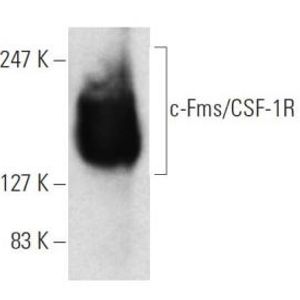

JAN 11, 2021ImmunologyMacrophages are a type of immune cell that can detect and destruct bacteria, viruses, and harmful materials. They a ...